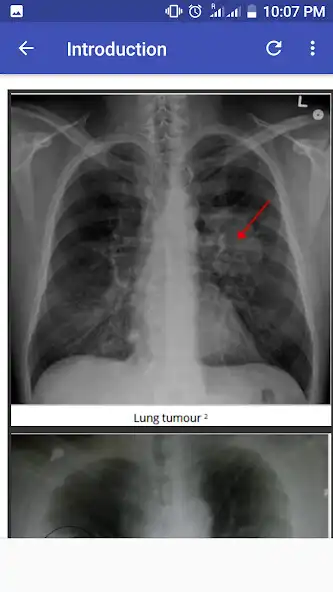

Interpreting Chest Xr-ay illustrated with cases of different pathological manifestation. It gives hint on how to comment on x-ray films. Alot of diseases has been discussed in each chapter.

Recent changes: This application made it very easy to Interpret chest x ray with illustrated 100 Cases.